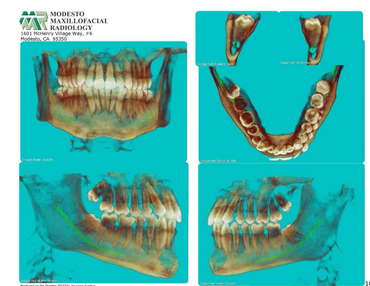

CBCT is a digital x-ray scanner specifically designed for scanning the head and jaws. The scanner rotates 360 degrees around the patient's head in a matter of seconds. The x-ray is a low energy fixed anode tube similarly used in panoramic machines. This method reduces radiation scatter common to most conventional x-rays. The cone shaped x-ray provides 360 views that can be presented in 2D image and 3D volume for advanced planning and diagnostic support.

This one scan provides more images than plain film conventional imaging, with complete visualization of the patient's entire maxillofacial region. These images clearly display TM disorders, impacted teeth, critical bone and tooth relationships, oral- nasal airways, para-nasal sinus, mandibular canal and difficult to see pathologies within one volume. The user friendly software system reconstructs true size, distortion free, high resolution images.

The CBCT scanner is fast, comfortable (nothing goes in the mouth), and painless for patients. It provides a complete set of maxillofacial images with less radiation than conventional orthodontic and medical type CT work-ups. CBCT now can re-create true size cephalometric and panoramic images, virtually eliminating the need for conventional orthodontic x-rays, so your patients will be comforted by the knowledge that you have all the information needed to evaluate and plan their treatment